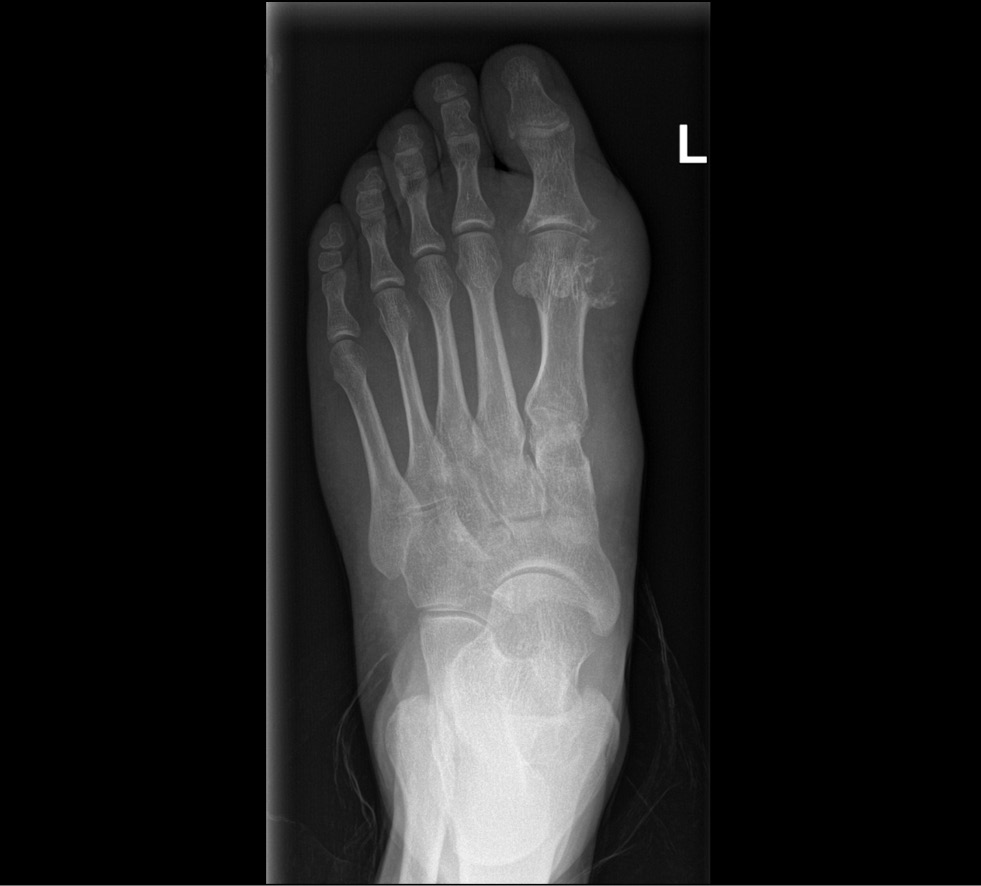

本文讨论了双能量计算机断层扫描的操作原理、其诊断准确性以及最常见的伪影类型。考虑了在双能量计算机断层扫描过程中,单钠尿酸盐沉积的存在对其他临床数据的可能依赖性,双能量计算机断层扫描在诊断痛风中的意义以及其在结晶性关节病的鉴别诊断中的作用。

与作为诊断痛风金标准的诊断性关节穿刺术相比,双能量计算机断层扫描有几个优点:无创性、执行速度、医源性并发症风险的多次减少。痛风的检测、治疗效果的监测、鉴别诊断的可能性,都是可以通过双能量计算机断层扫描来实现的。